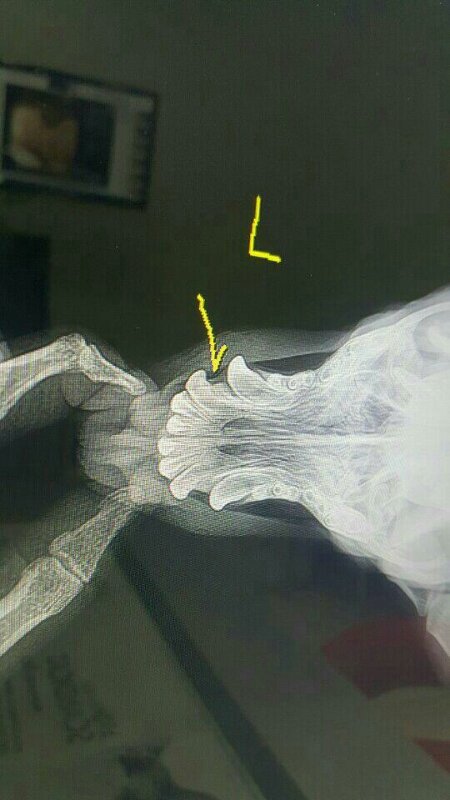

차를 돌려 2차선에 누워있는 아이를 조심히 갓길로 옮기고 상태를 보니 앞다리 하나가 덜렁거리고 입에 출혈이 나고 있었습니다.

다급히 병원으로 옮겨 검사결과 앞다리 골절과 턱에 금이간 상태였습니다.